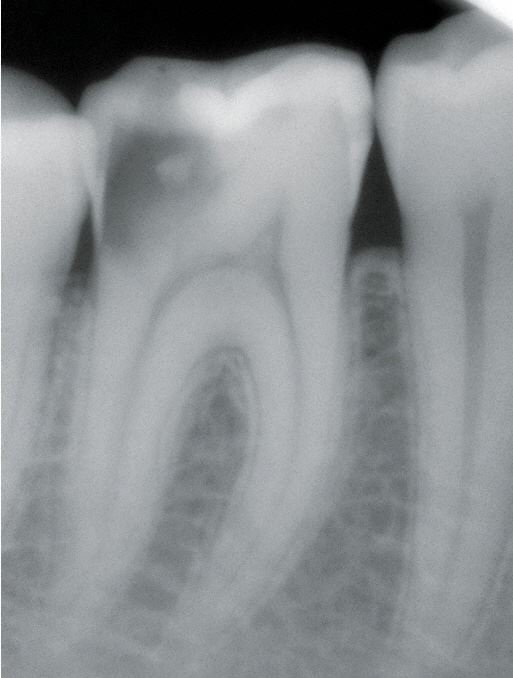

Röntgendiagnostik

Unterschieden werden initiale Karies, Dentinkaries sowie Fissurenkaries, Approximalkaries und Wurzelkaries.

Die klinische Untersuchung, insbesondere die visuelle Inspektion (Lupenbrille) sind Standard, um auch die "hidden caries zu erkennen. Zusätzliche Maßnahmen können Röntgenaufnahmen und Kariesdetektoren sein, um Frühstadien zu erkennen.